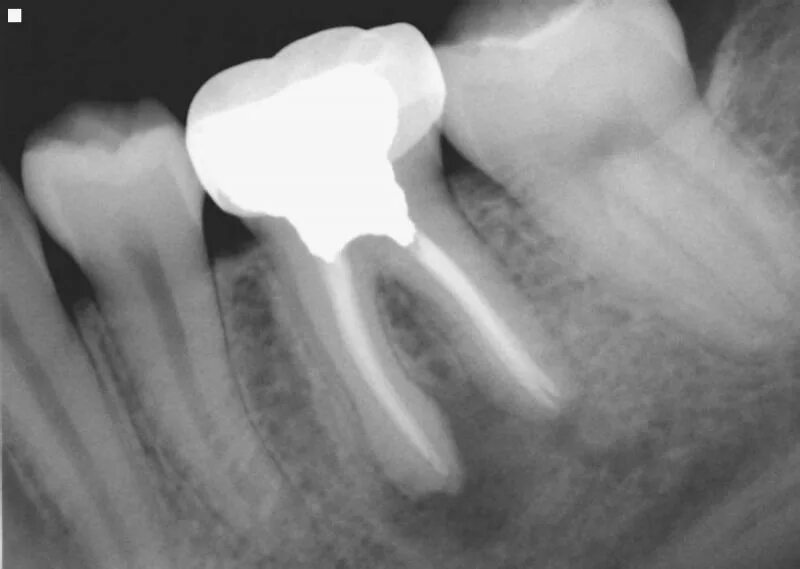

Давление под зубом